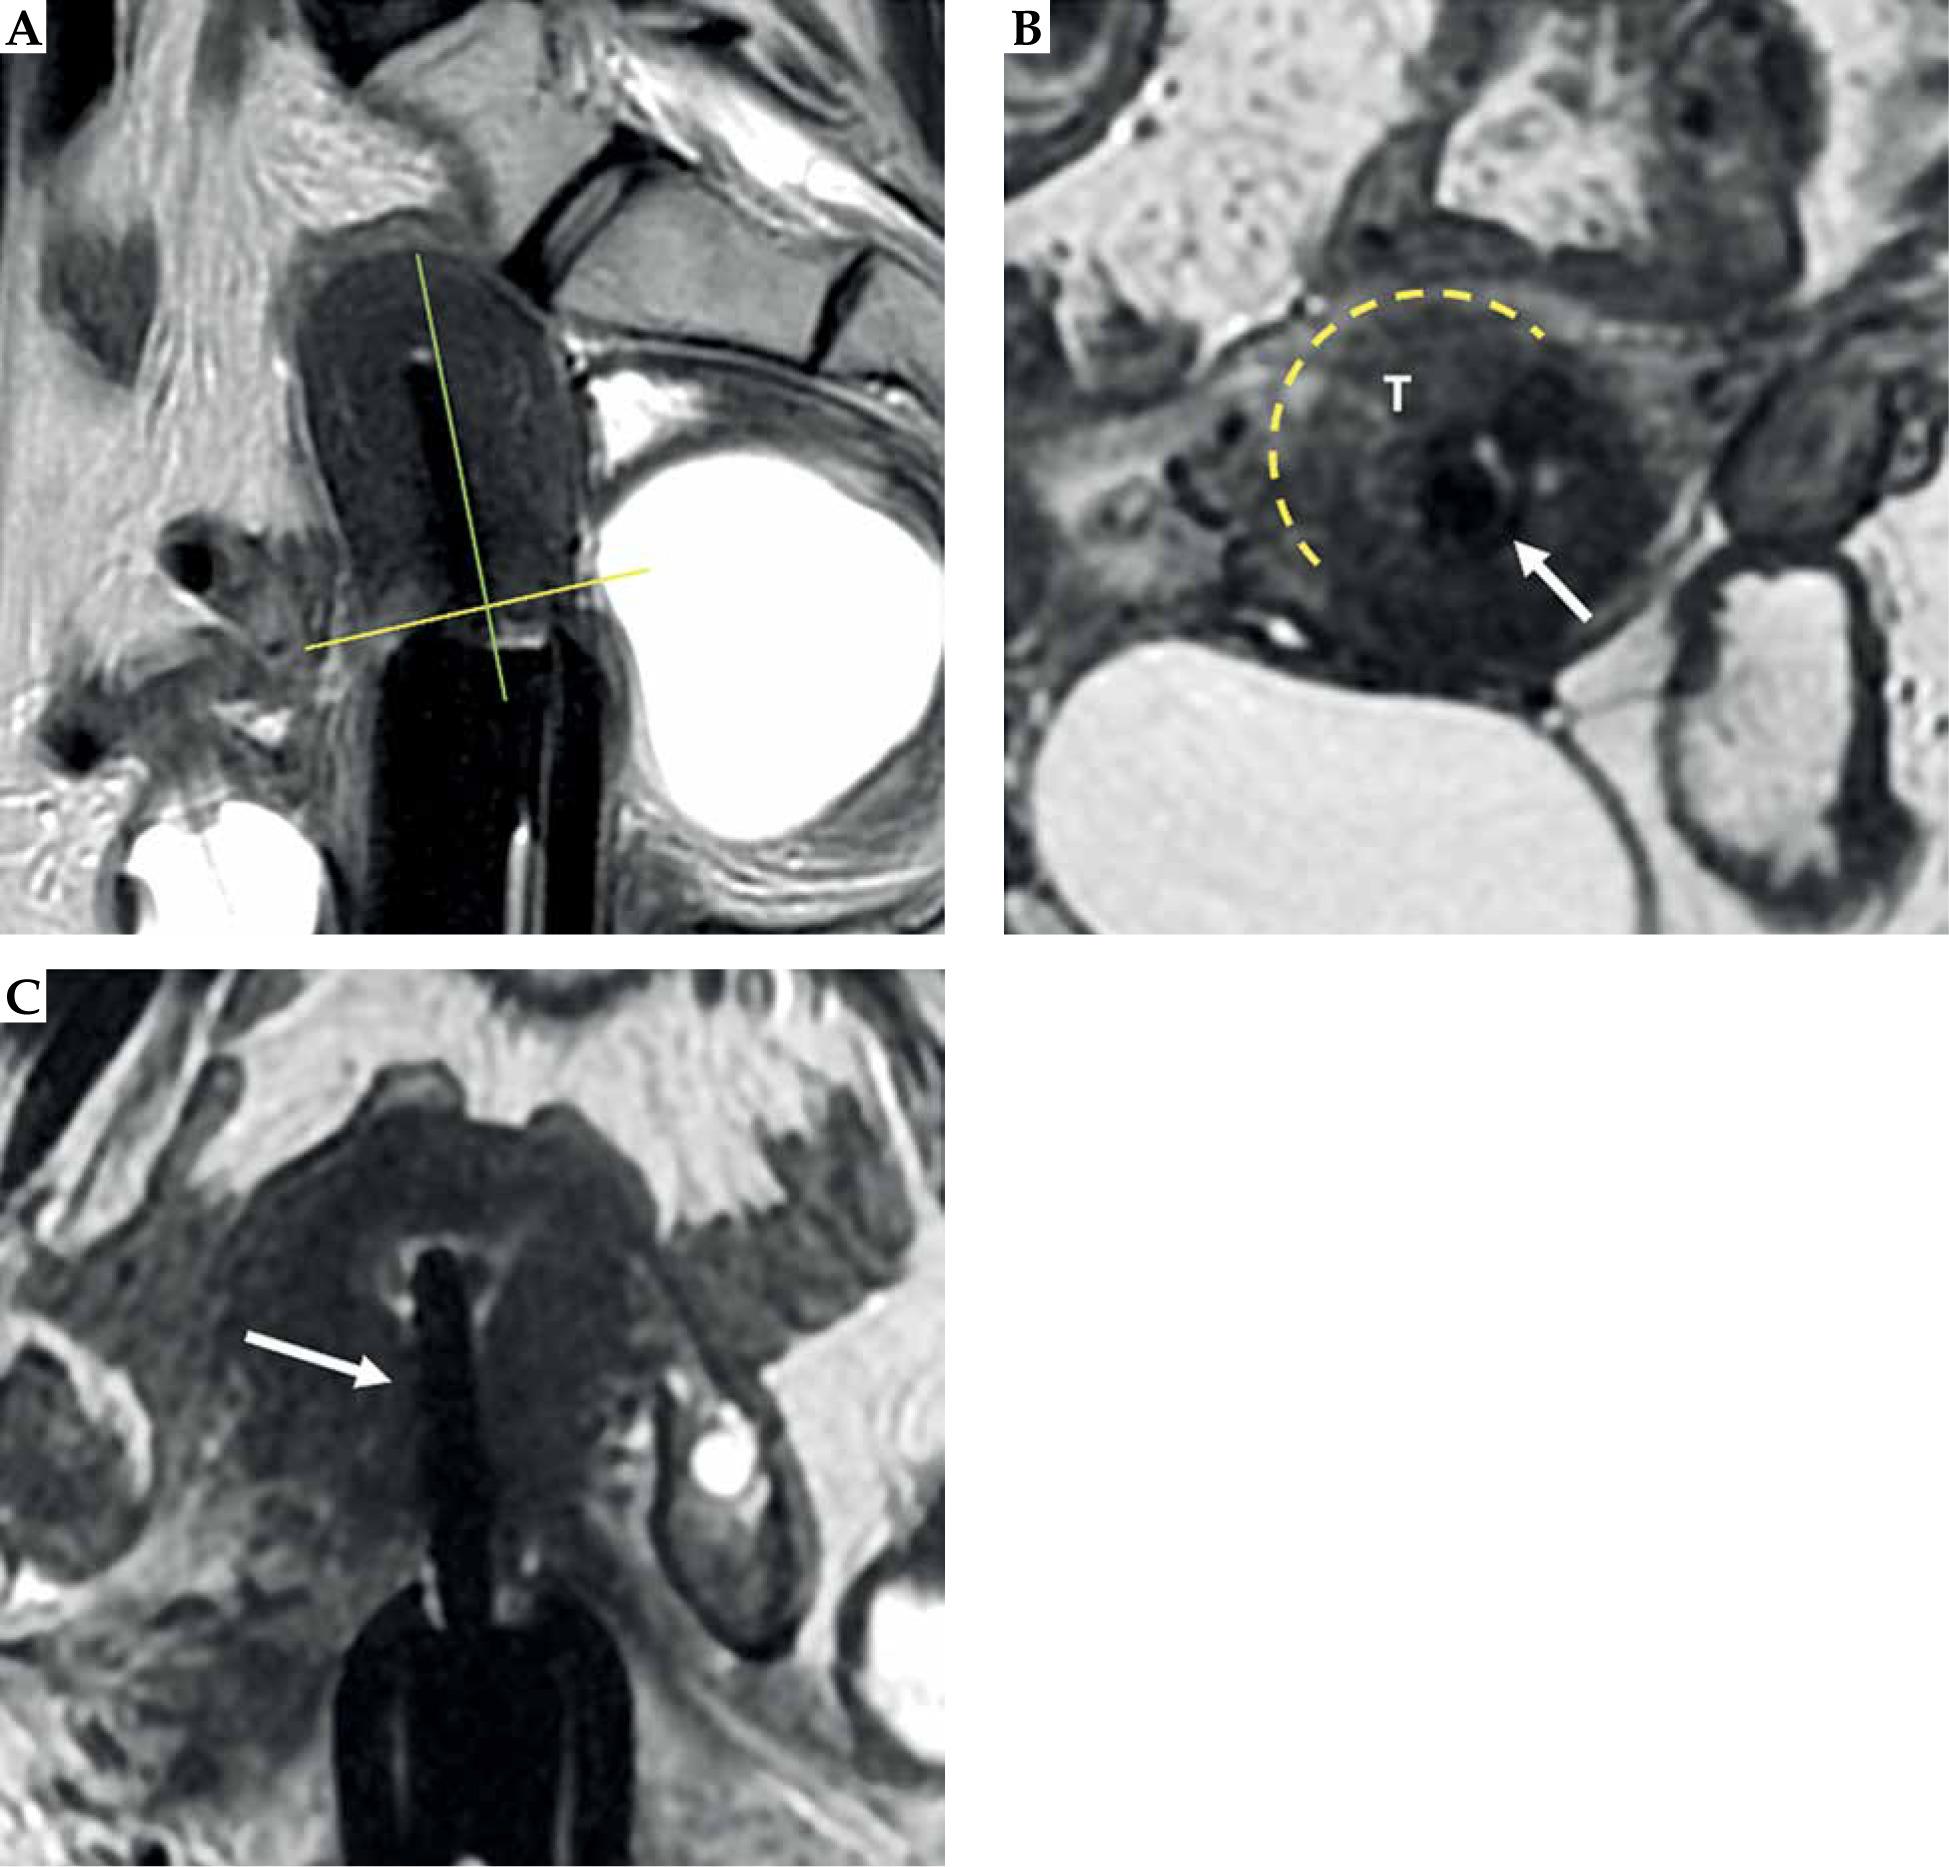

Fig. 8

Tumor maximum thickness: axial oblique T2-weighted FSE image perpendicular to the plane of the applicator (A) shows tumor extension within cervical stroma (arrow with maximum tumor extension (dotted line) from the tandem (arrowhead) within the cervical stroma at 9 o’clock) (B). Schematic illustration of the tumor maximum thickness (C)

Fig. 9

Maximum tumor length: coronal oblique T2-weighted FSE image in the plane with the applicator (A) shows maximum tumor length (dotted line) from the ring (*), along with the tandem (arrow) (B). Schematic illustration of the tumor maximum thickness (C)